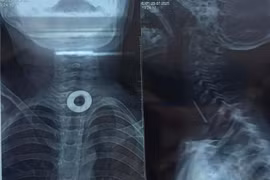

Chơi đùa, trẻ 7 tuổi nuốt phải kim loại 2cm kẹt trong thực quản

Hóc dị vật nhỏ triệu chứng đau không dữ dội nên dễ bị bỏ sót gây ra các biến chứng nguy hiểm như áp xe thực quản, thủng thực quản, vỡ áp xe, xuất huyết...